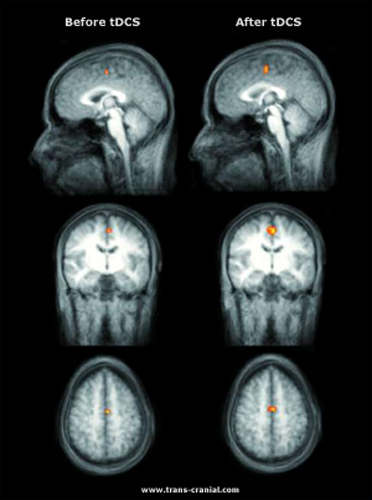

Изображение мозга (слева) и после (справа) транскраниальной стимуляции в ходе простого движения

– постукивания пальцами по крышке стола. Стимуляция повысила активность нейронов на 40%